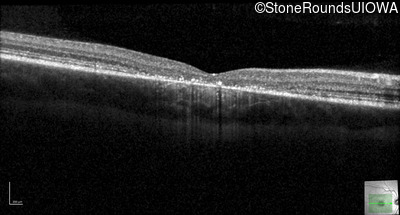

Optical Coherence Tomography - Right - 20/80 -1

Exemplar / OCT Stack